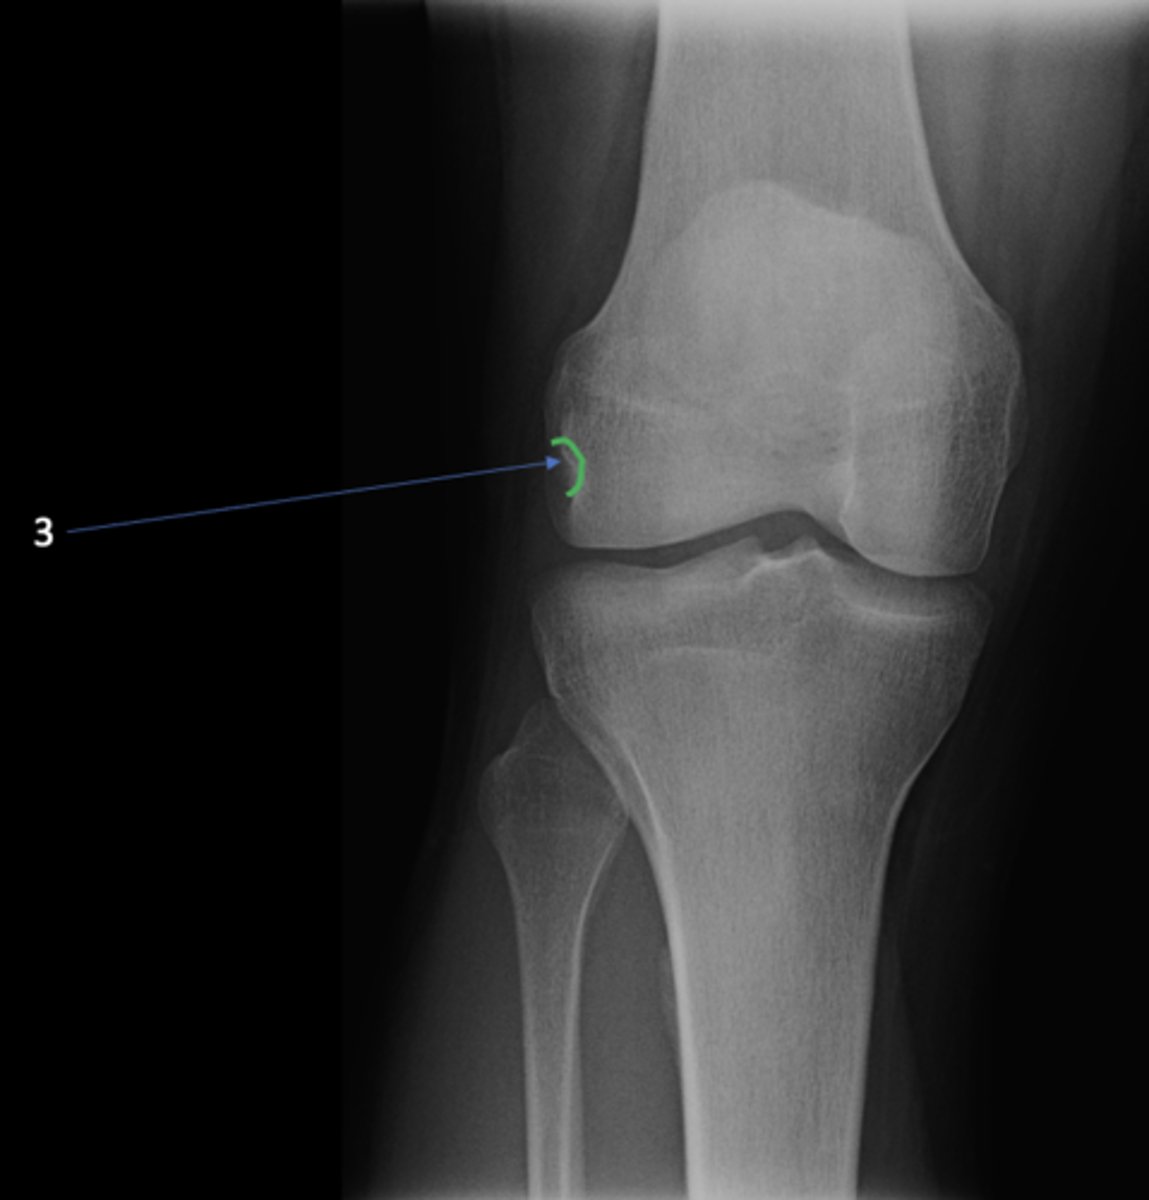

AP knee

View?

<p>View?</p>

49

New cards

Fibular head

ID 1

<p>ID 1</p>

50

Apex of fibular head

ID 2

<p>ID 2</p>

51

Fossa for popliteal tendon

ID 3

<p>ID 3</p>